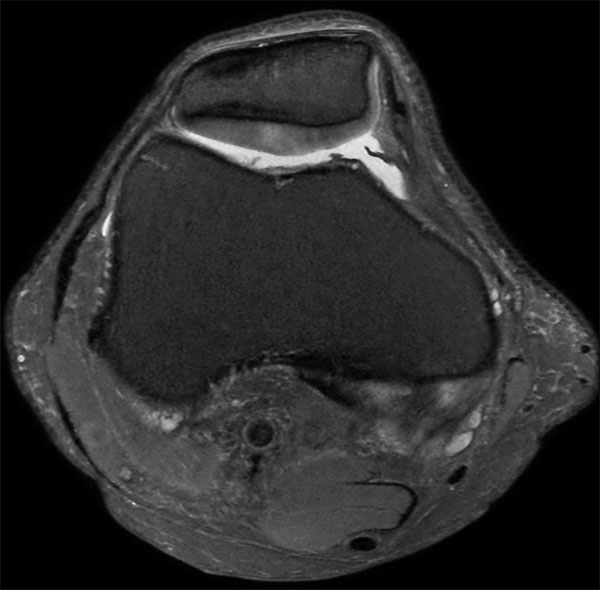

Knee Imaging with Cartilage Assessment

Middle aged board surfer presents with chronic knee pain. X-Ray shows no abnormalities. Follow-up MR examination requested.